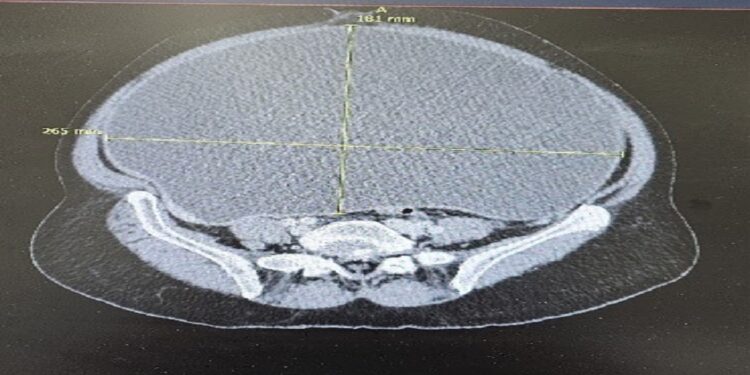

وبين أنه بعد إجراء العديد من الفحوصات المخبرية، والرنين المغناطيسي، والأشعة المقطعية، أظهرت النتائج وجود كتلة كيسية كبيرة في وسط وأسفل البطن، يُرجّح أن تكون ذات أصل مبيضي أو من الزائدة الدودية، وقد نمت الكتلة بمرور الوقت واحتوت على بعض الفواصل الداخلية والتكلسات، وبلغ حجم الورم في الزائدة الدودية 1.5 × 0.8 سم، وتمركز في قمة وجسم الزائدة مع امتداد مخاطي غير خلوي إلى السطح المصلي وغزو مباشر للمبيض الأيمن، الذي احتوى على كتلة كبيرة بحجم 25 × 23 سم ووزن يزيد عن 6 كغ، وتقرر إجراء عملية جراحية معقدة استغرقت أكثر من ست ساعات، أُجريت بدقة عالية لتجنب أي مضاعفات، وأسفرت العملية عن استئصال الورم بالكامل، إلى جانب الرحم وعنق الرحم والمبيضين والزائدة الدودية، مما أنهى معاناة المريضة التي استمرت لأكثر من خمس سنوات.